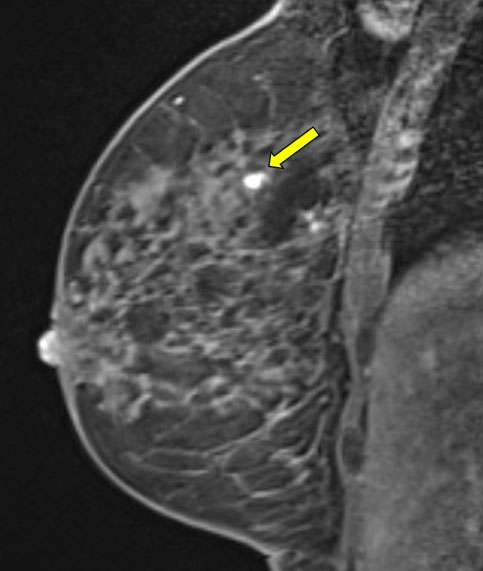

Procedure MRI Guided Breast biopsy Figure 3

Figure 3A and 3B. Sagittal T1-weighted fat saturated post contrast images demonstrate the biopsy tract and post sampling changes.

• Confirm biopsy of the target site with a post-biopsy scan (fig 3a and 3b)